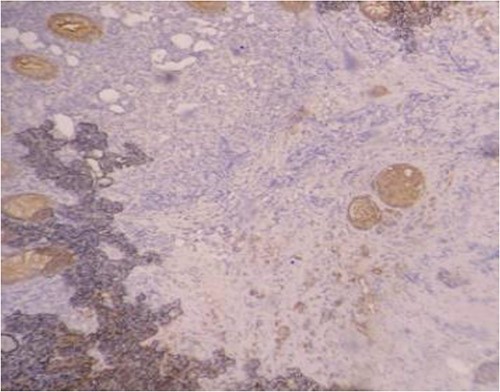

Serum carcinoembryonic antigen was 4.3 μg/L (normal value <5.1 μg/L). Biological tests showed normal platelet count and prothrombin time was 70%. Hemoglobin level was 12.2 g/dL. His biochemical tests showed hypoalbuminemia (31 g/dl). The patient was scheduled for a colonoscopy. However, a large bowel obstruction occurred during the bowel preparation. Thus, computed tomography (CT) scan of the abdomen and the pelvis was performed revealing circumferential wall thickening narrowing the rectal lumen and invading the prostate and the mesorectum with upstream bowel dilatation without extrinsic mass, lymphadenopathy, or metastasis. The patient underwent colostomy without incident. Colonoscopy was performed after colostomy, showing large, circumferential, infiltrative, friable, and stenosing submucosal mass with erythematous overlying rectal epithelium, taking on the appearance of grape clusters (shown in Fig. 1). Mucosal biopsies showed invasive poorly differentiated carcinoma referring at first a neuroendocrine tumor. Second mucosal biopsies were performed showing inflammatory modifications of the rectal mucosa without any malignancy. Third mucosal biopsies concluded to poorly differentiated carcinoma. Magnetic resonance imaging (MRI) of the pelvis showed circumferential wall thickening narrowing the rectal lumen and invading posterior peripheral area of the prostate, the bladder, the left seminal vesicle, and the mesorectum (shown in Fig. 2). The radiologist suggest a rectal cancer (RC) invading the urogenital tract or a PC invading the rectum subject to non-injected MRI. In fact, the MRI was interrupted before gadolinium injection because the patient was claustrophobic. Serum prostate specific antigen (PSA) was then ordered and it was raised at 25.59 μg/L (normal value<4 μg/L). Therefore, macro-biopsies of the rectal mucosa using snare loop were performed showing a poorly differentiated infiltrative carcinoma and immunohistochemical (IHC) stains were strongly positive for PSA and pancytokeratin and negative for anti-CD56 (shown in Fig. 3). Then, a clear diagnosis of PC invading the rectum was established. Bone scintigraphy was performed and was normal. The patient was referred to urology department. He underwent surgical castration. Then, androgen depletion therapy (ADT) was started. A total of 3 months later, there was a good response with his PSA level dropping to 0.5 μg/L. About 3 years after, patient is still alive, but PSA level has increased to 52 μg/L. The CT scan of the thorax, the abdomen, and the pelvis showed a prostatic hypertrophy with loss of the security edging with the rectum without any metastatic involvement.

In our case, the patient experienced digestive symptoms without any lower urinary tract symptoms. Colonoscopy findings were uncommon showing a circumferential, infiltrative, friable, and stenosing submucosal mass, taking on the appearance of grape clusters. In historically reported cases, the diagnosis of PC was confirmed by histology obtained by endoscopic ultrasound with transrectal needle biopsy of the prostate or surgical biopsies [6]. In our case, PC invading the rectum was suspected after CT scan and MRI. Serum PSA was not requested in the beginning but seeing the radiological findings; it was ordered and was high suggesting a PC. Histology was not contributive initially at three times, what prompted us to perform macro-biopsies of rectal mucosa showing a poorly differentiated infiltrative carcinoma. The IHC stains were strongly positive for PSA.

The use of prostate-specific IHC stains in biopsies and serum PSA are useful in differentiating between the two. PSA is an important tool for early detection and differential diagnosis of PC, with a sensitivity and specificity of 92.30% and 40.81%, respectively [7]. In a case reported by Liu et al. [8], the pathologist performed prostate specific stains on the biopsies upon seeing a poorly differentiated, infiltrative carcinoma. They were positive for PSA and Alpha-methylacyl-CoA racemase (AMACR: a mitochondrial and peroxisomal enzyme overexpressed in PC). In fact, the diagnosis of PC invading the rectum is not always easy. In a review of the histopathological slides of 20 cases of PC found on colorectal biopsies by Lane et al. [9], it was found that it was difficult to differentiate between the two based on the histology itself. The authors recommended ruling out a prostatic origin when faced with a poorly differentiated carcinoma in a rectal biopsy with the use of prostate specific IHC stains.